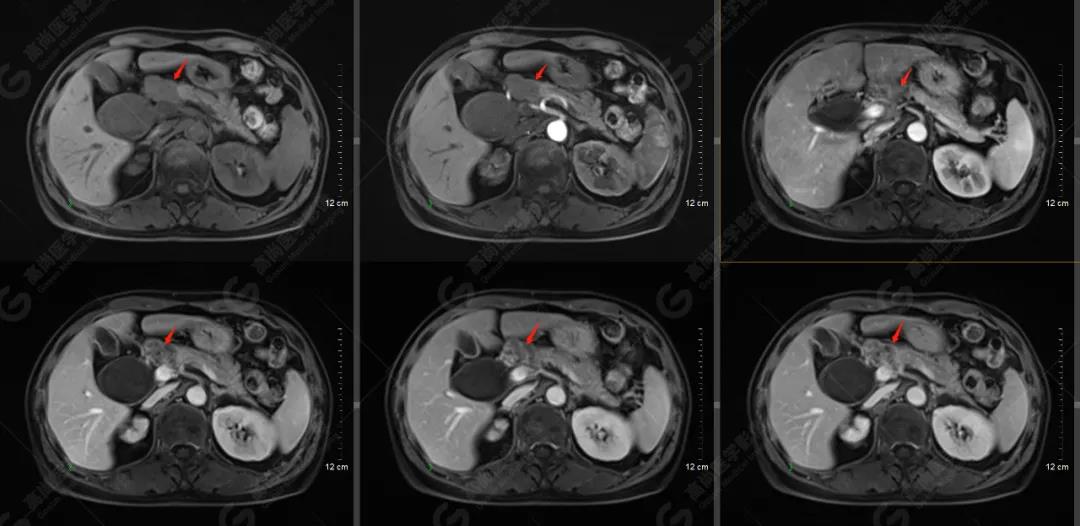

MR檢查所見(jiàn):胰頭可見(jiàn)結(jié)節(jié)狀異常信號(hào)影,大小約2.5×1.8cm,T1WI呈稍低信號(hào),T2WI呈略高信號(hào),信號(hào)欠均勻,DWI可見(jiàn)彌散受限,病灶與周圍正常胰腺組織分界欠清,Gd-DTPA增強(qiáng)掃描病灶呈明顯不均勻強(qiáng)化;病灶相應(yīng)節(jié)段上方膽總管明顯囊腫擴(kuò)張,大小約6.4×4.0cm。肝內(nèi)膽管輕度不均勻擴(kuò)張,以左支為著,呈軟藤征。胰管未見(jiàn)擴(kuò)張。胰頭上緣及腹膜后(腹主動(dòng)脈旁)見(jiàn)腫大淋巴結(jié),增強(qiáng)掃描可見(jiàn)中度強(qiáng)化,部分強(qiáng)化不均勻;腹腔未見(jiàn)積液。

提示: 胰頭占位性病變,性質(zhì)考慮為胰腺癌并胰頭上緣、腹膜后多發(fā)淋巴結(jié)轉(zhuǎn)移

肝內(nèi)膽管輕度擴(kuò)張,膽總管囊狀擴(kuò)張